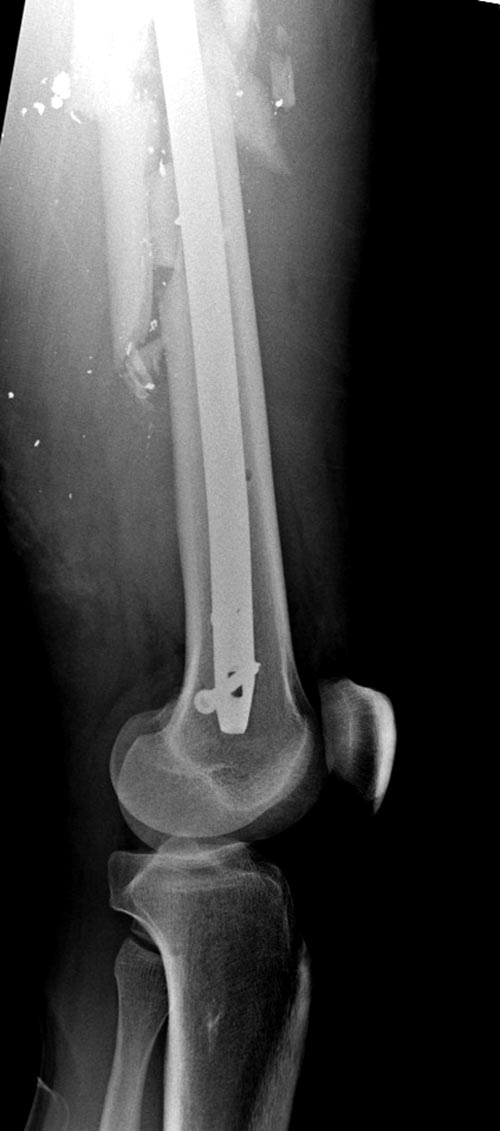

На снимках осложнение огнестрельного перелома бедра поздней инфекцией. 7

лет назад оперирован: правое бедро, сперва на ExFix, затем заменен на

гвоздь, а левая - гвоздь при поступлении.